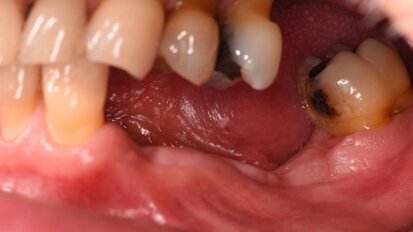

Rehabilitace Straumann